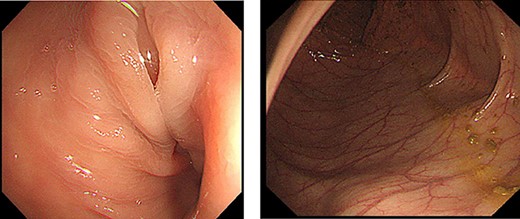

Endoscopic examination showed that the site of torsion was near the sigmoid rectum (Fig. 1), and a computed tomography(CT) scan revealed prominent dilatation of the oral bowel (Fig. 2).

CT findings. CT showed dilation of the oral intestinal tract was observed.